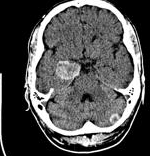

This is a 68 year old woman with a history of esophageal cancer who was previously treated with chemotherapy and radiation therapy followed by surgery. She has no evidence of extracranial disease. She presents with a headache. An MRI is obtained which demonstrates a 5 cm lesion in the right frontal lobe with a 15 mm midline shift.

This is a single metastases, controlled primary, high performance status. Her RPA category is I, indicating a significantly longer median survival at 7.2 months. She also has a midline shift in an accessible area. Her options are:

This patient is a surgical candidate and needs prompt correction of a lesion causing mass effect and mid-line shift. Surgical intevention is the fastest way to do this. Therefore surgical intervention is required unless the patient refuses surgery. If the patient refuses surgery, then whole brain radiation may be considred appropriate in either 30 Gy or 37.5 Gy doses at conventional fractionations. An RTOG study however, demonstrated that surgery followed by whole brain radiation therapy improved outcomes. Thus there is only one real choice, assuming the patient is a surgical candidate and is willing to undergo surgery.